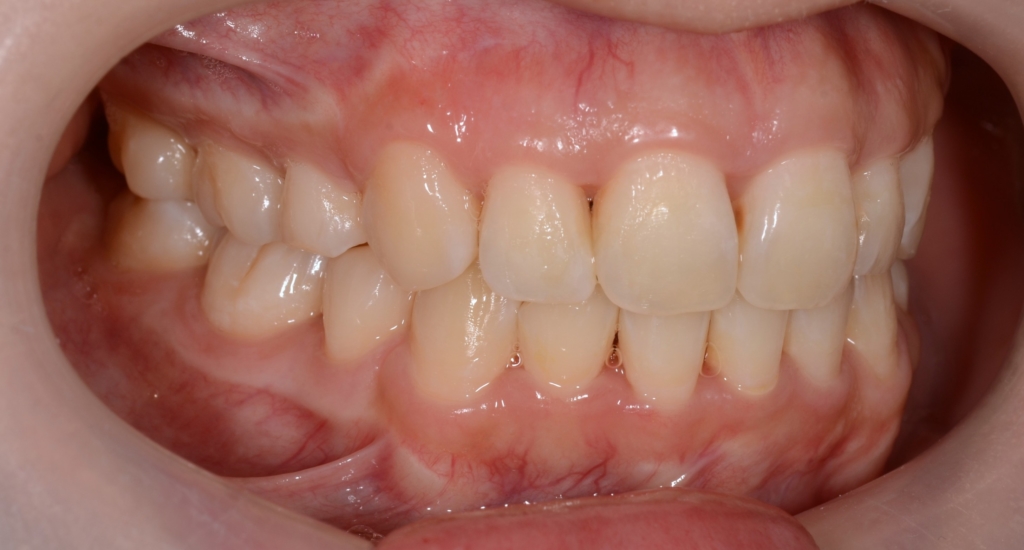

患者さんは、20代の女性(社会人)です。

「八重歯などのガタガタを治してきれいな歯並びになりたい!」

というのが一番の希望でした。

合わせて、お口を楽にすると開いてしまい、上の前歯が見えてしまうのも何とか出来れば嬉しい!とのことでした。

#1.顎と歯の不調和による叢生

#2.上顎前突(出っ歯)